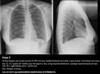

Diagnose?

A

Venstresidig basal pneumoni